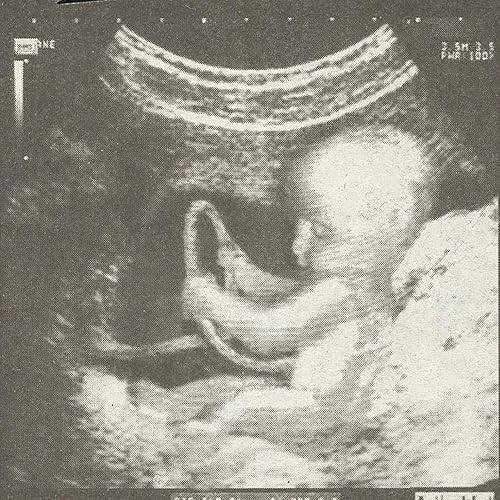

Bebe In Utero Semaine 14 16 Sa La Boite Rose

Evolution Voici Un Bebe A 16sa Puis Un Echographie 3d Bebe Art Echo Facebook

Bonjour Pour Rappel Un Echographie 3d Bebe Art Echo Facebook